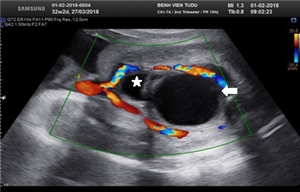

CLS: Hội chứng song thai thiếu máu đa hồng cầu